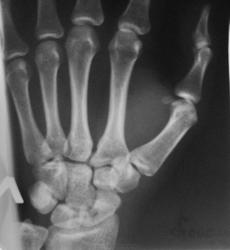

Случай №2 Молодой спортсмен, около 6 месяцев назад упал на руку. Лечился. Ставили перелом ладьи.Вопрос только в том: "А сросся ли он?". Нет ли тут асептического некроза?

Консолидация четко прослеживается. Пациента что-то беспокоит?

А во втором... Консолидация есть однозначно. Об этом говорит хотя бы одно то, что за полгода при занятиях спортом не произошло вторичного смещения отломков (или полгода была иммобилизация?). Асептического некроза не нахожу.

Во 2 случае - оба снимка надо бы выполнять, когда предплечье параллельно кассете в т.ч. А так фасетка луча становится эллипсом и позиционируется на ладью, особенно в косой проекции. Кистовидная перестройка в зоне консолидации перелома тела ладьи без ее деформации. Боль при отсутствии явной костной патологии может исходить из окружающих мягкотканных структур, разнообразием которых наградил Бог человеческую кисть, дабы тот мог в поте лица зарабатывать себе на хлеб насущный не только тяжелым ратным трудом, но и творческими профессиями, требующими тонкой моторики рук.